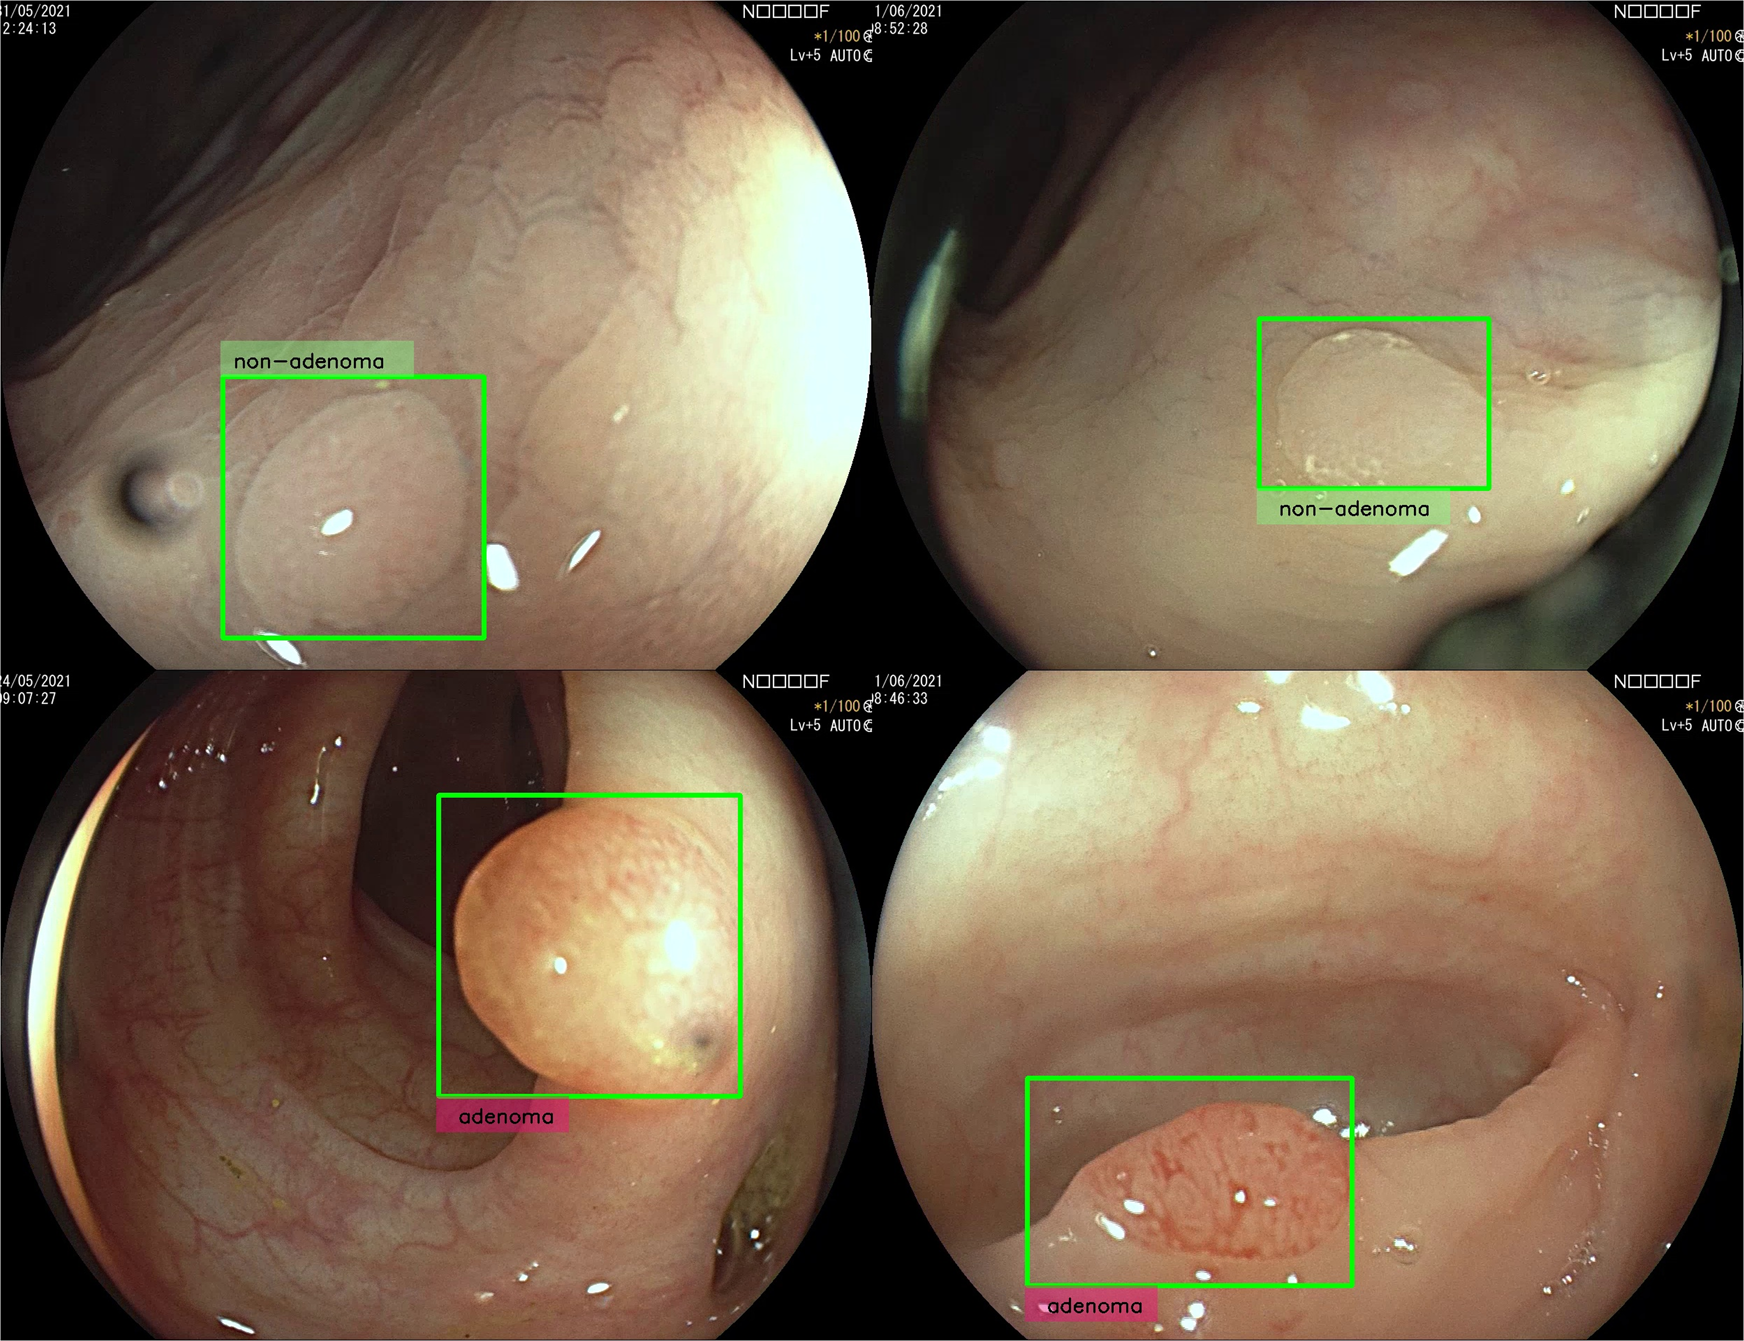

- GI-Genius团队,使用白光(WL)内窥镜视频流实时(50-60ms延迟)无缝进行息肉的CADx。

- 人机比对:使用在线平台,分为10名专家和11名非专家内窥镜师,二分类:”腺瘤性“与”非腺瘤性息肉“。

- Four types of different predictions can be produced by the algorithm: “adenoma”, “non-adenoma”, “no-prediction” or “analysing”. “analysing” is printed near the polyp to communicate to the endoscopist to keep imaging the target polyp until the minimum number \(N_m\)(预先设定) of frames is reached.